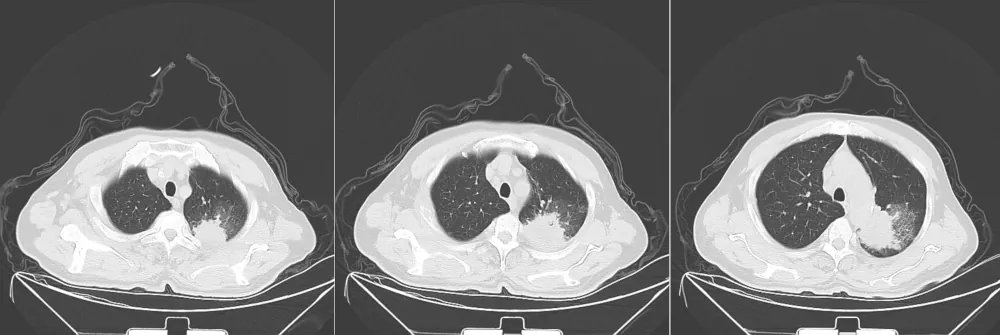

Sample CT Image

Sample CT scan image

Source: National Cancer Institute - The Cancer Imaging Archive (TCIA)

This sample image is provided for demonstration purposes only.

There is a large abnormality in the left lung, manifesting variably as consolidation with surrounding ground-glass opacities predominantly in the left lower lobe or as a densely necrotic-appearing mass primarily in the left upper lobe with extension to middle and lower lobes and associated volume loss. A moderate left pleural effusion is noted in some views, mainly in dependent portions. There is a subtle ground-glass opacity in the upper right lung, possibly representing a small pneumothorax. The right lung is otherwise clear.

1. Large left lung abnormality with variable features suggestive of either pneumonia/consolidation (with possible atelectasis) or primary lung malignancy (necrotic mass); significant discrepancy in lobe predominance and characterization warrants urgent clinical correlation.

2. Possible moderate left pleural effusion and small right apical pneumothorax (less certain findings).